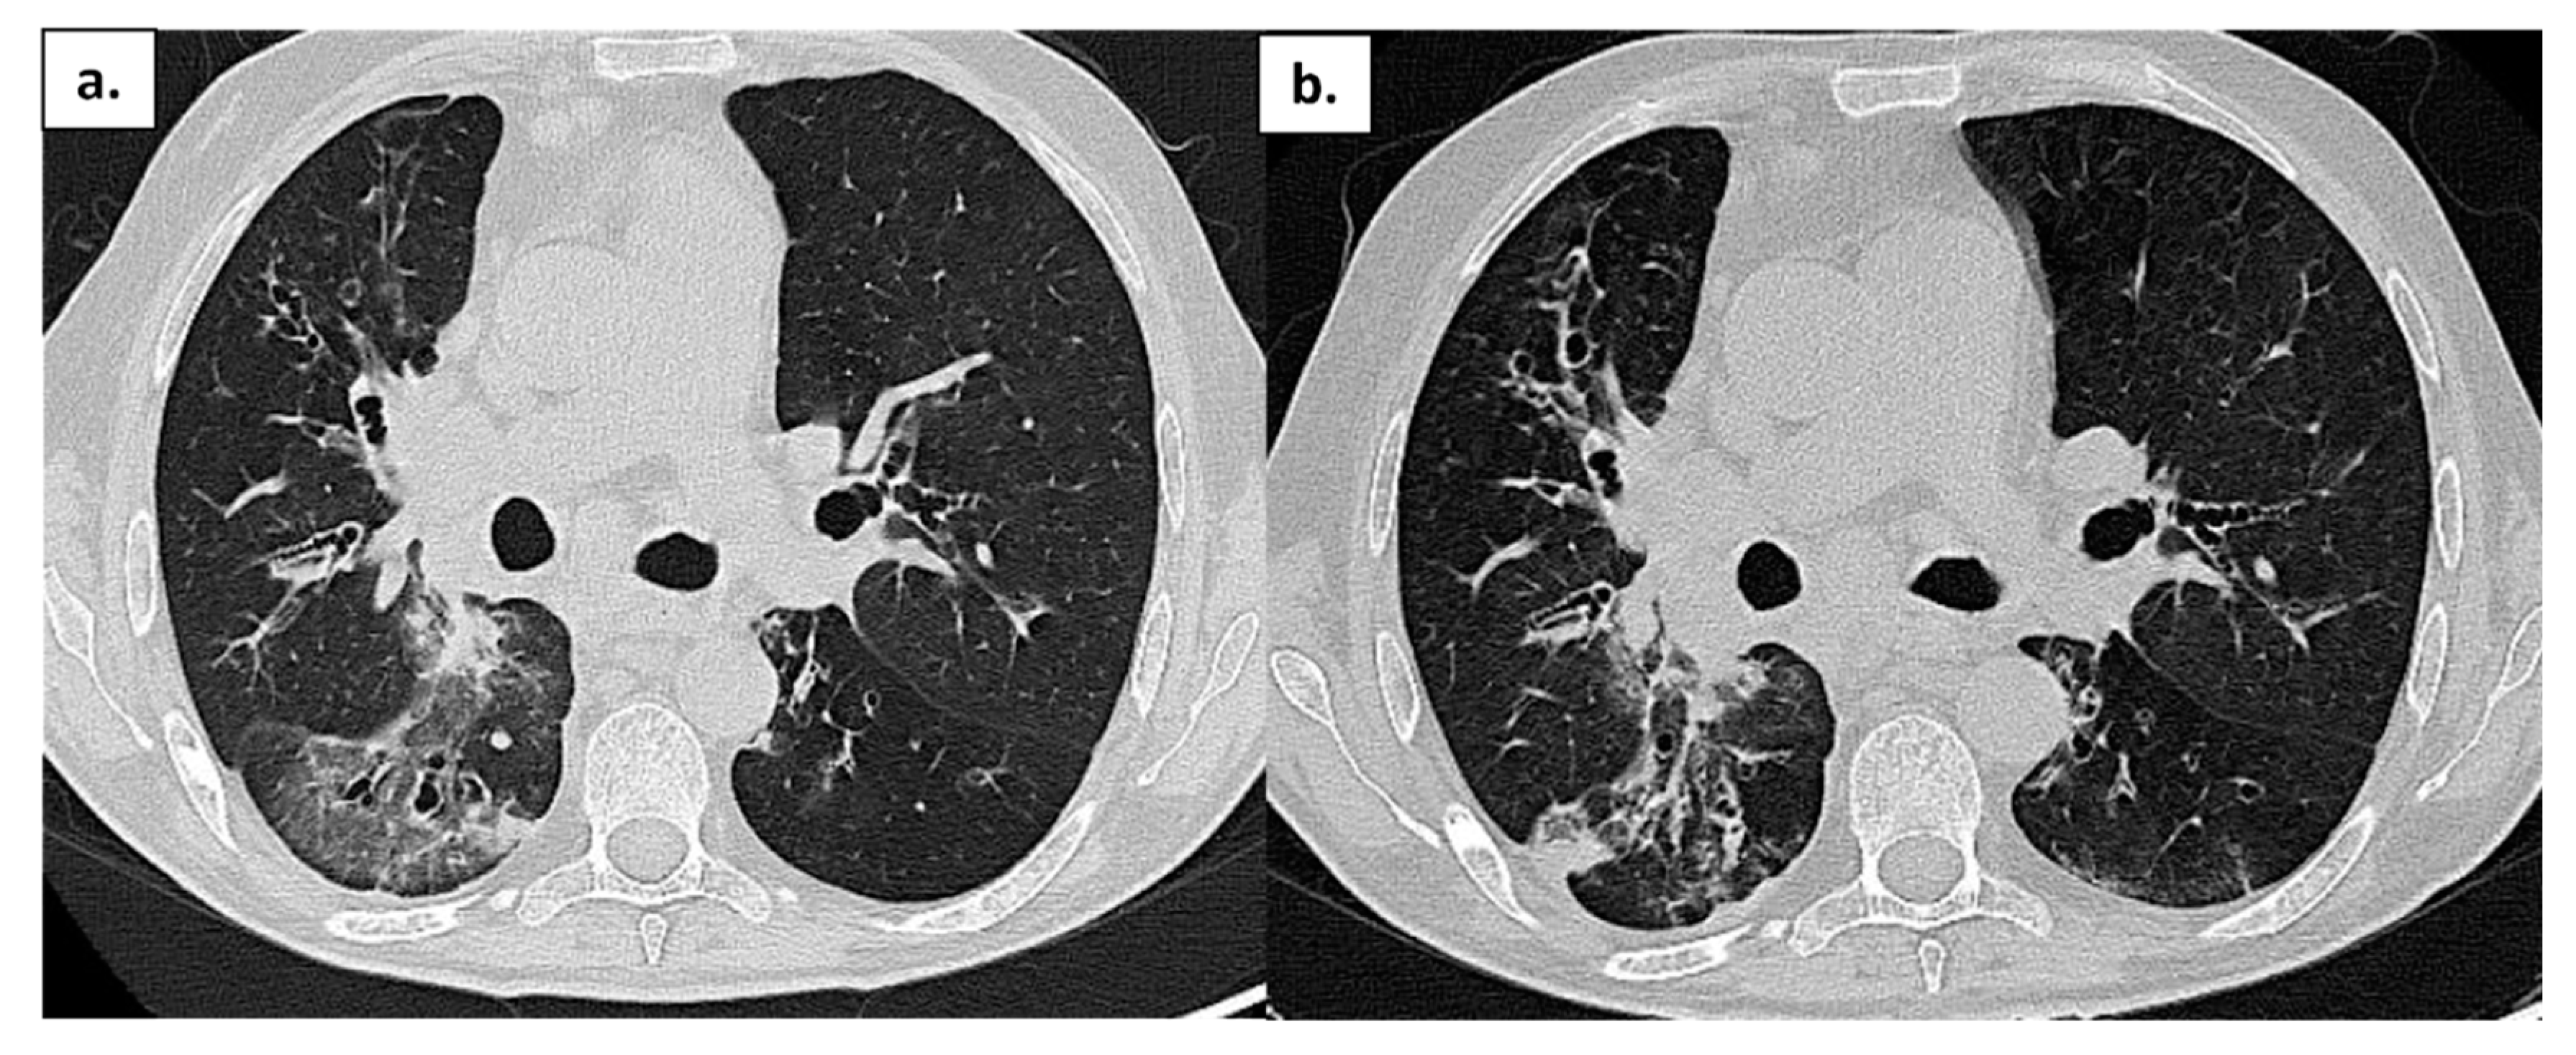

| Comorbidity | RA | Splenomegaly, bronchiectasis; recurrent viral infections | Hypertrophic cardiomyopathy; AF; CKD secondary to nephrolithiasis. C | Bronchiectasis; COPD; EBV-related NHL | GLILD; Bronchiectasis; colonization Aspergillus; Sjogren syndrome; CKD |

| SARS-CoV-2 related pneumonia | yes | yes | yes | yes | no |